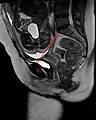

The pelvic inlet or superior aperture of the pelvis is a planar surface which defines the boundary between the pelvic cavity and the abdominal cavity (or, according to some authors, between two parts of the pelvic cavity, called lesser pelvis and greater pelvis). It is a major target of measurements of pelvimetry.

Its position and orientation relative to the skeleton of the pelvis is anatomically defined by its edge, the pelvic brim. The pelvic brim is an approximately apple-shaped line passing through the prominence of the sacrum, the arcuate and pectineal lines, and the upper margin of the pubic symphysis.